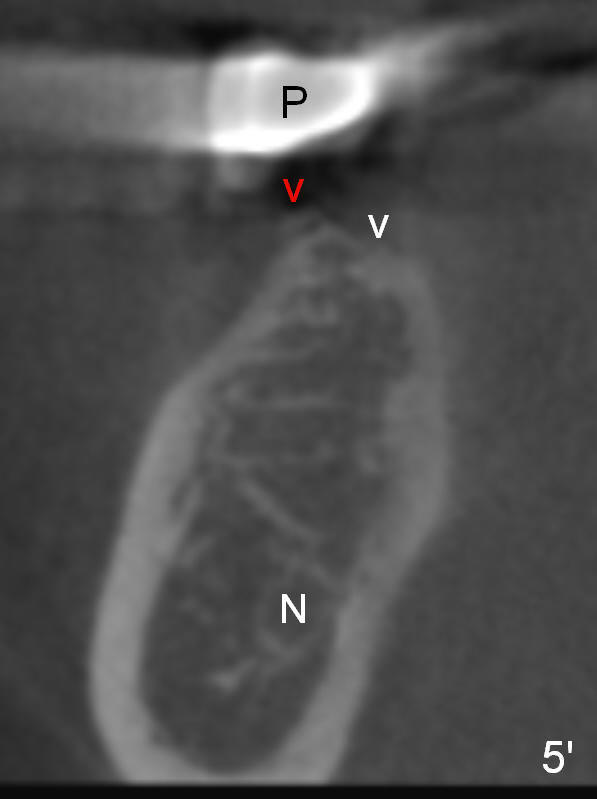

The posterior 3-unit should be able to dislodge (Fig.2). Check whether there is the similar lesion associated with #28 (<). The tooth #31 should be afforded not to be restored, since there is a small inlay prep mesially.